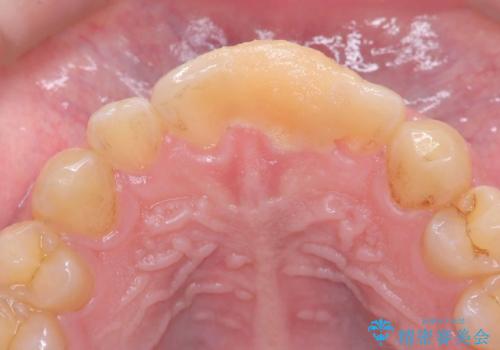

サーフィンで前歯をぶつけて歯が欠けた|かかりつけ医で治療困難と言われ当院へ来院|VPT(生活歯髄療法)で神経を保存|前歯の見た目も改善

- 歯冠破折により点状露髄を認めました。破折から1週間以内であったこと、また歯髄診断により生活反応が良好で保存可能と判断したため、VPT(生活歯髄療法)を行い神経の保存を試みました。